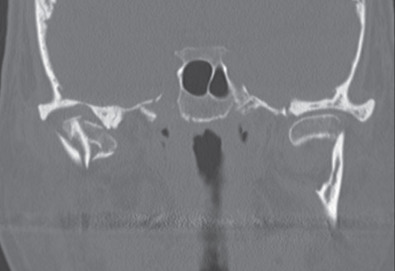

The main limitation of plain radiographs is that they do not give three-dimensional details of the fracture. Computed tomography (CT) is almost universally available today and most patients will already have a scan performed by the emergency department before a surgical consultation is made. CT gives extremely good detail of the position of the fracture(s) and the displacement of the segments. It is especially good for intraarticular fractures ( Fig. 1.15.6 ). CT scans cannot show the position of the intraarticular disk but the need to have that information available for treatment planning purposes is a hotly debated topic (discussed later). Should one desire more information on the position of the disk, a magnetic resonance imaging (MRI) scan would be needed as this is the imaging modality that provides the best view of the disk and other soft tissues within the joint.

CT scans of two completely dislocated condylar process fractures. Note that the articulating surface of the condyle is not in contact with the articulating surface of the glenoid fossa.